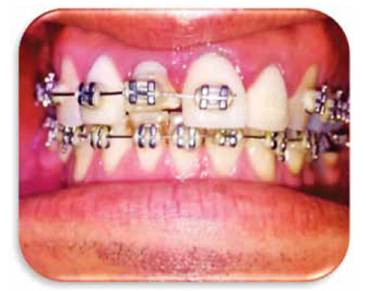

Una vez realizada la fibrotomía se procede a reposicionar el bracket y se deja en control durante 4 meses para lograr estabilizar el movimiento (por cada milímetro de extrusión se debe dejar 1 mes ferulizado, en este caso se logró extruir unos 4 mm aproximadamente. (Figuras 13A y 13B)

Figura 13A: Extrusión del incisivo de unos 4 mm.

Figura 13B: Recolocación nuevamente del bracket y colocación de alambre ortodóntico.